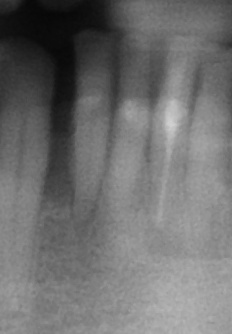

圖三為拔除之下顎側門齒,可見牙根處仍有許多的牙結石,因此治療無望,圖四為立即植牙後的情形,這時流血已完全停止,而齒槽骨與人工植第之縫隙再使用合成人工骨粉修復之,圖五為一週後牙肉之恢復情況

圖三 |